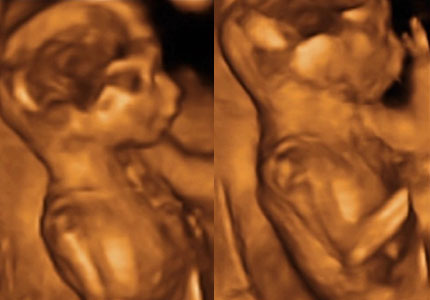

[quote="dorkamartini"]a írta:dorkamartini második kettős képen miután kortyolgatott éppen mosolyog és mivel direkt ettem fincsi édeset előtte így látni a mellette levő képen ahogy kidugja a nyelvét mert aaaaannnnyira fincsi:))))))